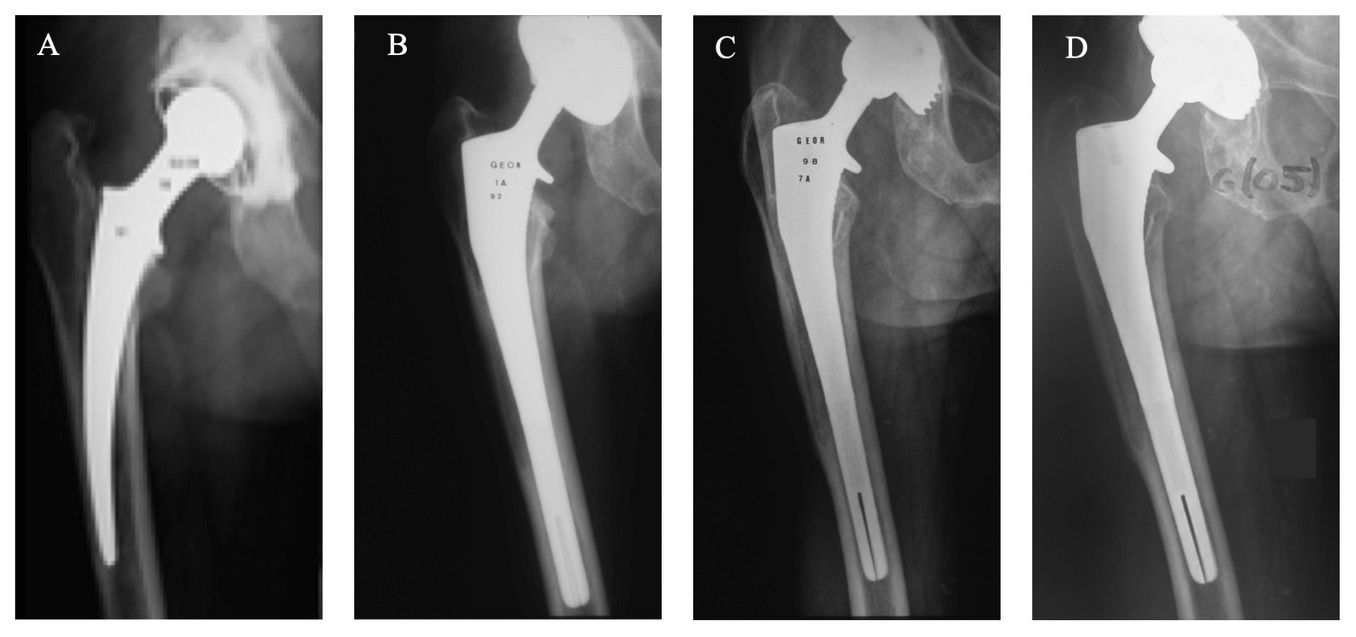

Successful femoral reconstruction with a cementless stem requires immediate axial and rotational stability, as well as close contact between the implant and the living host bone to promote osseointegration and definitive fixation. In patients with little to no bone loss (Paprosky types 1 and 2A femurs), our preferred implant is the CORAIL stem (DePuy, Johnson & Johnson, Warsaw, IN), a grit-blasted straight device of quadrangular cross-section entirely plasma-sprayed with a 150-µm layer of pure HA (Fig. 1a). This stem has proved its value in primary hip arthroplasty [10]. In patients with substantial bone loss (Paprosky types 2 and 3A), our preferred implant is the KAR stem (DePuy), especially designed for revision cases. The KAR stem is 25% longer than the CORAIL stem to bridge bone defects or occasional windows, and to provide a greater bioactive area for contact with host bone to facilitate osteointegration [7] (Fig. 1b). However, the KAR stem has the same proximally flared pattern as the CORAIL stem, with the addition of two distal slots in the sagittal and coronal planes to reduce global rigidity and prevent stress risers in the cortex at the tip of the stem. In patients with very severe deficiencies (Paprosky types 3B and 4), our preferred implant is the REEF stem (DePuy), as it provides immediate distal fixation (Fig. 1c). The REEF is a modular device composed of two main elements. The more distal element is metaphyseo-diaphyseal; conical in its proximal part and cylindrical in its diaphyseal part. The proximal zone is 100 mm long, with horizontal macrostructures to increase the contact surface and to prevent subsidence. The distal zone, of variable length, has a slight bow to prevent anterior cortical contact, longitudinal grooves to enhance osseointegration, and several horizontal holes for locking with 5-mm diameter screws. The more proximal element is a metaphyseal component fitted onto the stem with a Morse taper. This neck unit allows the surgeon to fine-tune anteversion within the confines of the existing metaphyseal bone and to restore leg length. In addition, this segment has an optional trochanteric claw that can be fixed to stabilize the greater trochanter and to improve the lever arm of the gluteal muscles if required.

Though aseptic loosening is the most common reason for revision THA (Fig. 2), the indications for revision using HA-coated stems include several other diagnoses as: intertrochanteric fracture with cerclage of the greater trochanter, periprosthetic fracture, tumor resection, extensive osteolysis, and reimplantation in one- or two-stage exchange arthroplasty for the treatment of chronic infection at the site of THA. Implant revision for pain and severe stress shielding has also been discussed by some authors.